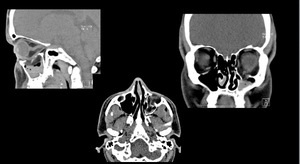

Jellemzői a CT az orrmelléküregek előnye, jelzések, árnyalatok CT

Levezető CT orrmelléküregek lehetővé teszi, hogy ne csak objektíven értékelni az állam a melléküregek, hanem, hogy a feltétele a könnycsatornát, Arc-és homloküreg üregek. Továbbá, ez a módszer a vizsgálat során tályogok, kóros. És mind a veleszületett és szerzett eredményeként a sérülések. Nagy szerepe CT olyan esetekben, amikor a műtét szükséges betegségek különböző jellegű orr helyet, amennyiben jelenlétük vezethet szövődmények a műtét során, vagy megnehezítik beteg felépülése a műtét után.

Amikor végzett CT sinus eljárások egy személy kap egy adag sugárzás egy kis összeget. Ez főként annak a ténynek, hogy a nagyon eljárást, amelyet végzett a spirál CT, nem tart tovább, mint 10 perc alatt. Csak egy bizonyos idő után az újbóli vizsgálat megengedett. Ez annak a ténynek köszönhető, hogy a orrmelléküregek található közel az agy, így a felmérést kell végezni nagyon óvatosan.